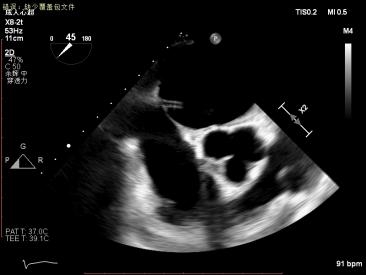

1.四腔心切面和二腔心切面可见左室高侧壁室壁瘤形成,二尖瓣瓣叶脱垂伴重度反流。

3D MV View: 二尖瓣前后瓣叶对合不全,A2/P2稍偏1区可见未闭间隙。PISIA主要来源于A2/P2区域。